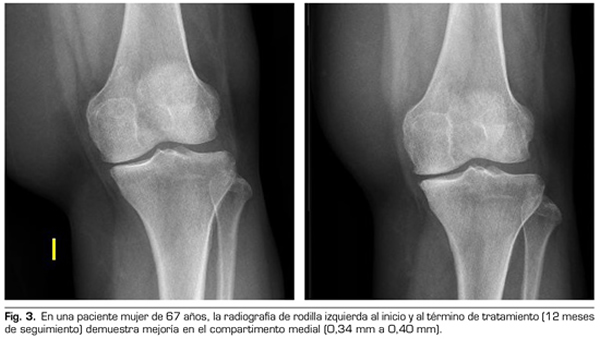

Variables radiológicas: en 53 pacientes analizados radiológicamente (según protocolo estandarizado) al año de seguimiento después del tratamiento con ozono, el compartimento interno aumento significativamente de 4.12 ± 1.41 mm a 4.4 ± 1.35 mm (p = 0.0008) y el compartimento externo aumentó de 6 ± 1.37 a 6.16 ± 1.4 mm (p = 0.0753).

Figura 3